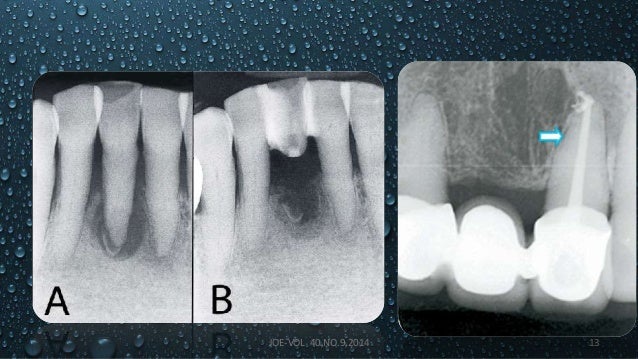

Treatment outcome of the Teeth with Cemental Tearsv -DR ...

Treatment outcome of the Teeth with Cemental Tearsv -DR ... from image.slidesharecdn.com